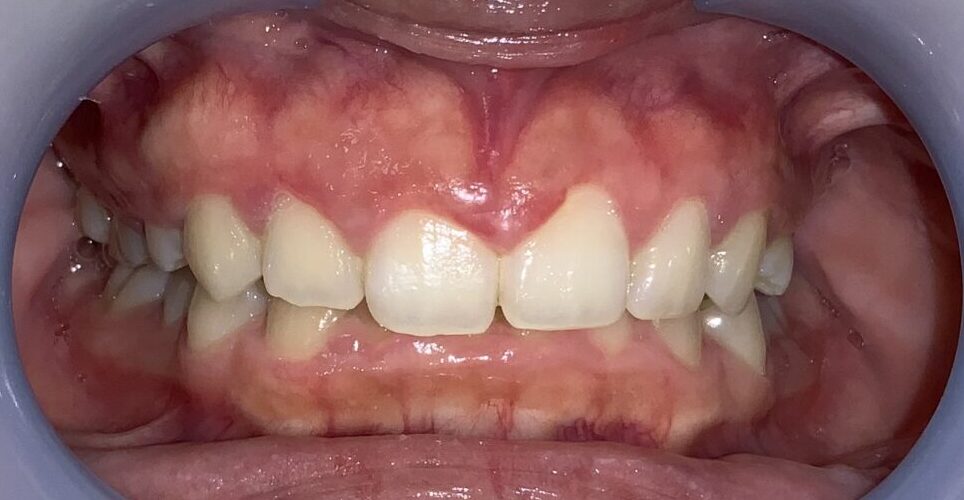

手術前の状態から見て参ります。

歯ぐきが被っており、歯が小さく、左右差があります。歯ぐきが被っている影響で歯ブラシの清掃が届かないので、プラークの堆積や歯ぐきの発赤も認められます。

過蓋咬合(かがいこうごう)の状態です。上の歯並びが下の歯並びを大きく被せてしまい、上の歯並びに隠れてしまい下の前歯が全く見えません。